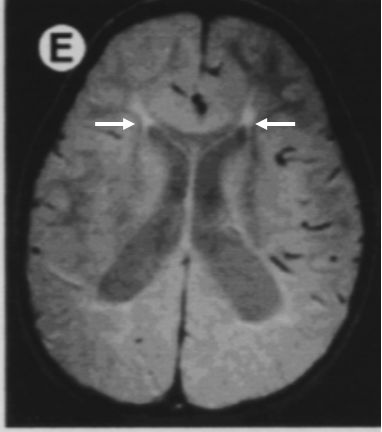

早产儿脑损伤(periventricular leukomalacia, PVL)

2、B超:HIE早期检查(72小时内),有助于了解脑水肿,脑室内出血、基底节、丘脑损伤和脑动脉梗塞等病变类型。

3、CT:生命体征稳定后检查,生后4-7天为宜,有病变者3-4周复查,要排除新生儿脑发育过程中正常的低密度现象

4、MRI:对病变性质和程度评价优于CT,对矢状旁区和基底节损伤的诊断尤为敏感。多层面成像,分辨率高,无放射性损害,但所需时间长、噪音大、费用高